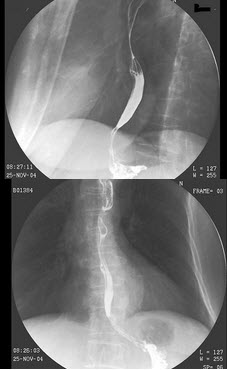

25、单项选择题

女,50岁,血便10余年,加重1年(连续出血),近2月大便时肛门常滴鲜血,量较多,X线检查如图,最可能的诊断是()

A.直肠癌

B.直肠绒毛状腺瘤

C.直肠淋巴瘤

D.直肠转移癌

E.直肠结核

60、单项选择题

男,50岁,进食梗阻1年,结合图像,最可能的诊断为()

A.食管下段癌

B.贲门癌

C.食管静脉曲张

D.贲门失弛缓

E.胃底癌